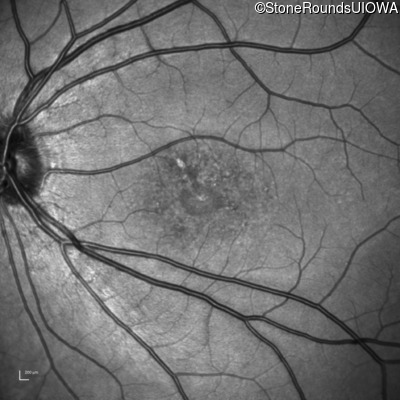

AR Stargardt Disease (IIA)

Age at visit: 20 years

Age at visit: 22 years

This 20 year old man first noticed some difficulty reading the board at school in 9th grade 20 in 2017